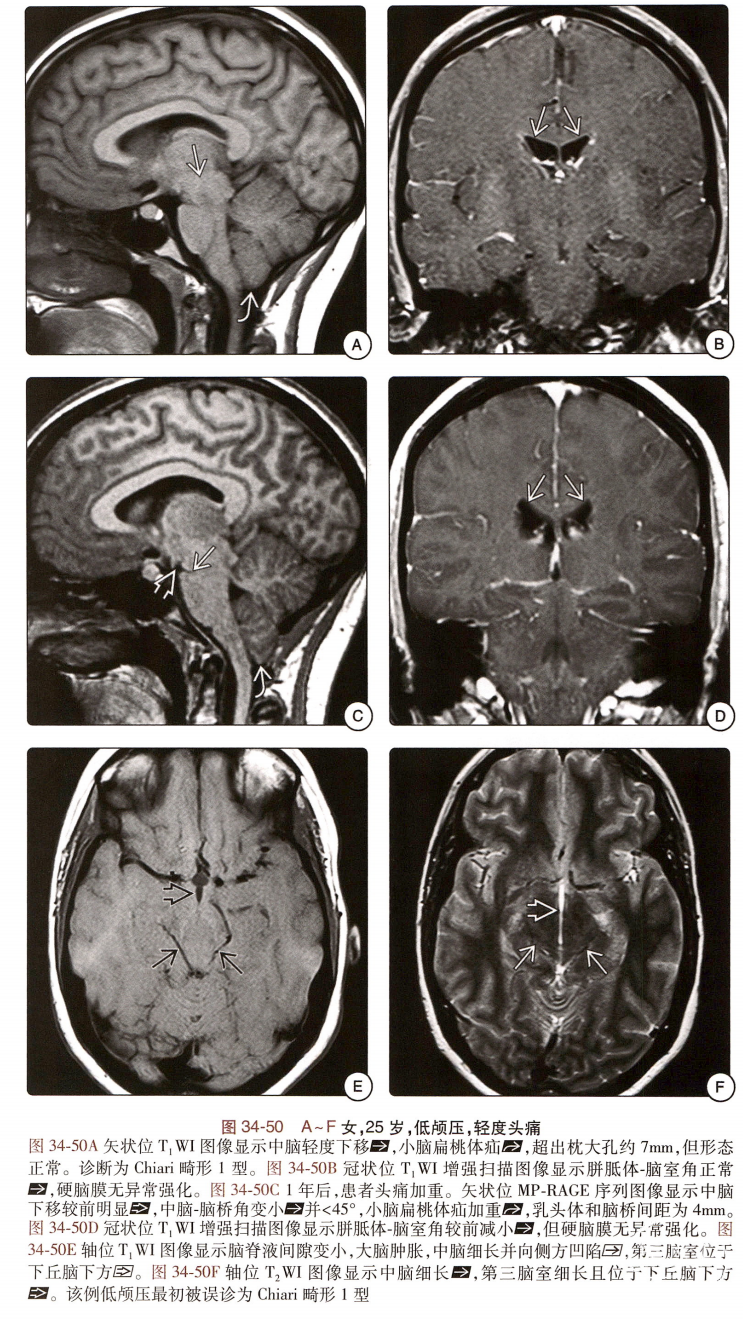

低颅压综合征